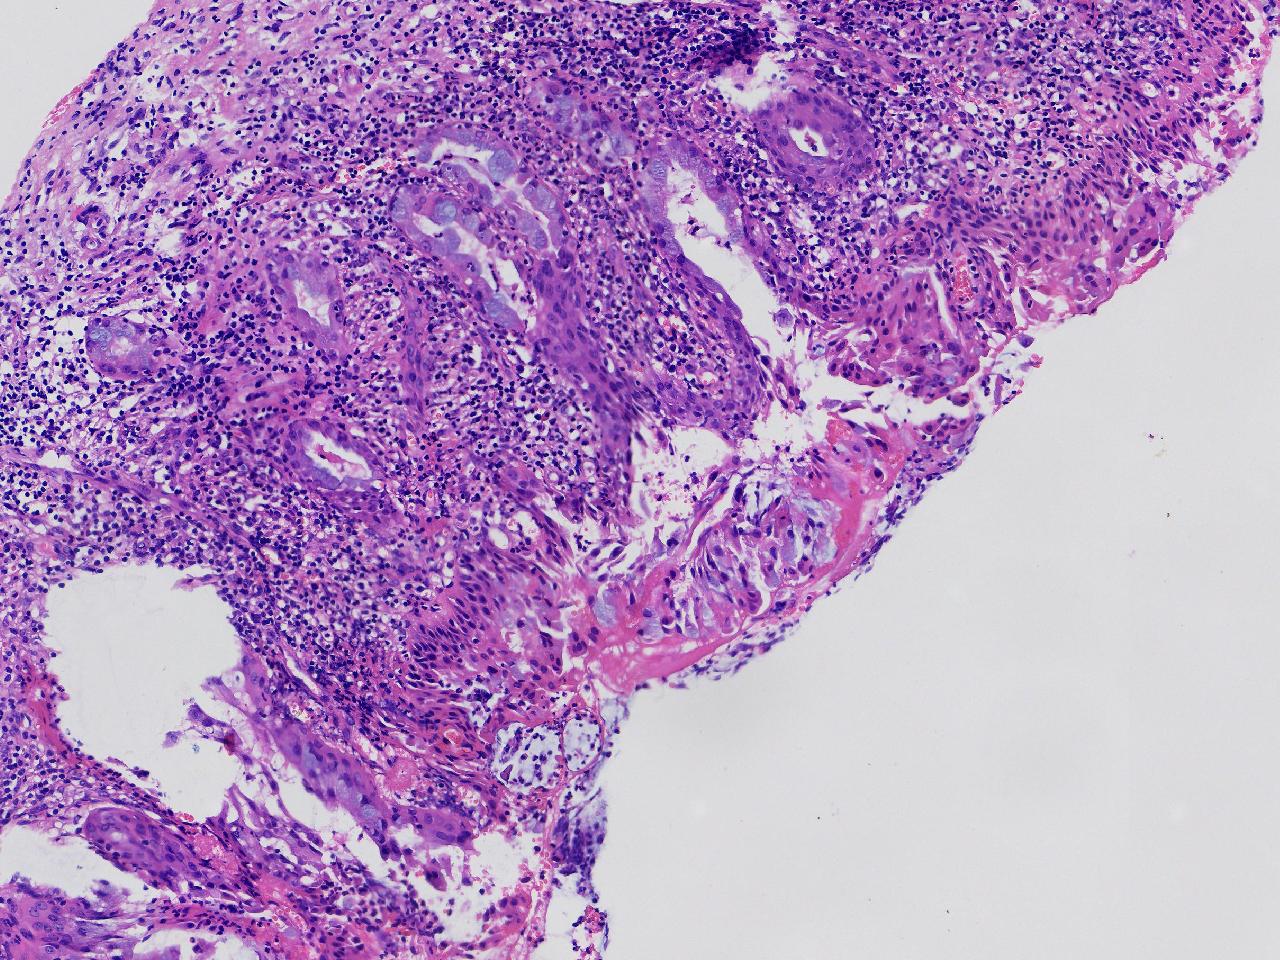

CIN1级? CIN2级?

女,41岁,宫颈活检,HPV16(+)

宫颈多点活检。

灰白色不整形软组织多块。

图2

慢性宫颈炎伴鳞化,建议定期复诊

慢性炎,储备细胞增生伴鳞化,